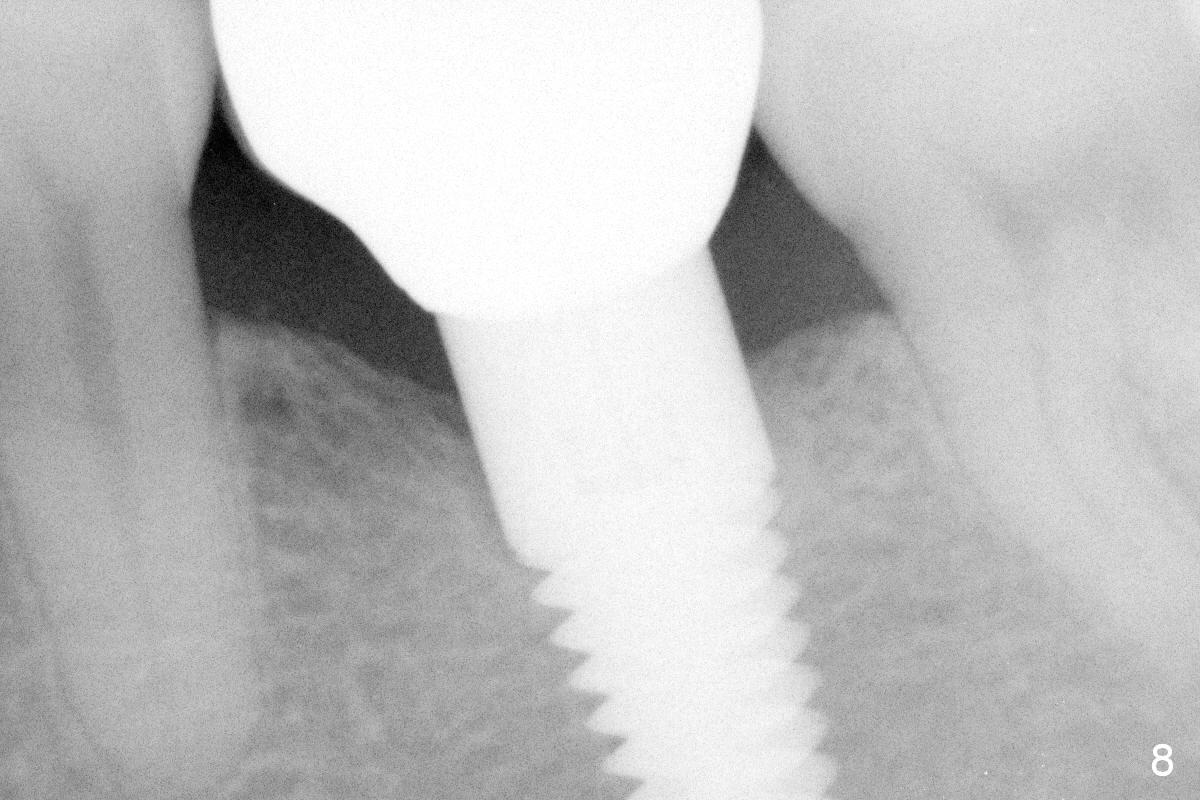

The mesial and distal crests of the tooth #19 were even for a 50-year-old man 7 years ago. Three years later, swelling developed around the distal root with bone loss (Fig.2 *). Three months later, localized swelling occurred (Fig.3 *) with oozing. The patient had thrombopenia (platelet 40 K). The tooth was extracted with suture. There is distolingual root tip resorption. Two months and a half later (Fig.4), a 6x17 mm implant was placed (Fig.5). The implant osteointegrated 5 months postop (Fig.6). The distal crest re-appears 5 months (Fig.7), 2 years (Fig.8) and 2 years 8 months (Fig.10) post cementation. At the last appointment, the patient complained of pain and swelling at #30 with mesial bone loss (Fig.10 *), as compared to Fig.9 taken 9 years ago. The mesiolingual pocket is deep. After scaling and Chlorhexidine irrigation, Arestin is locally administered.